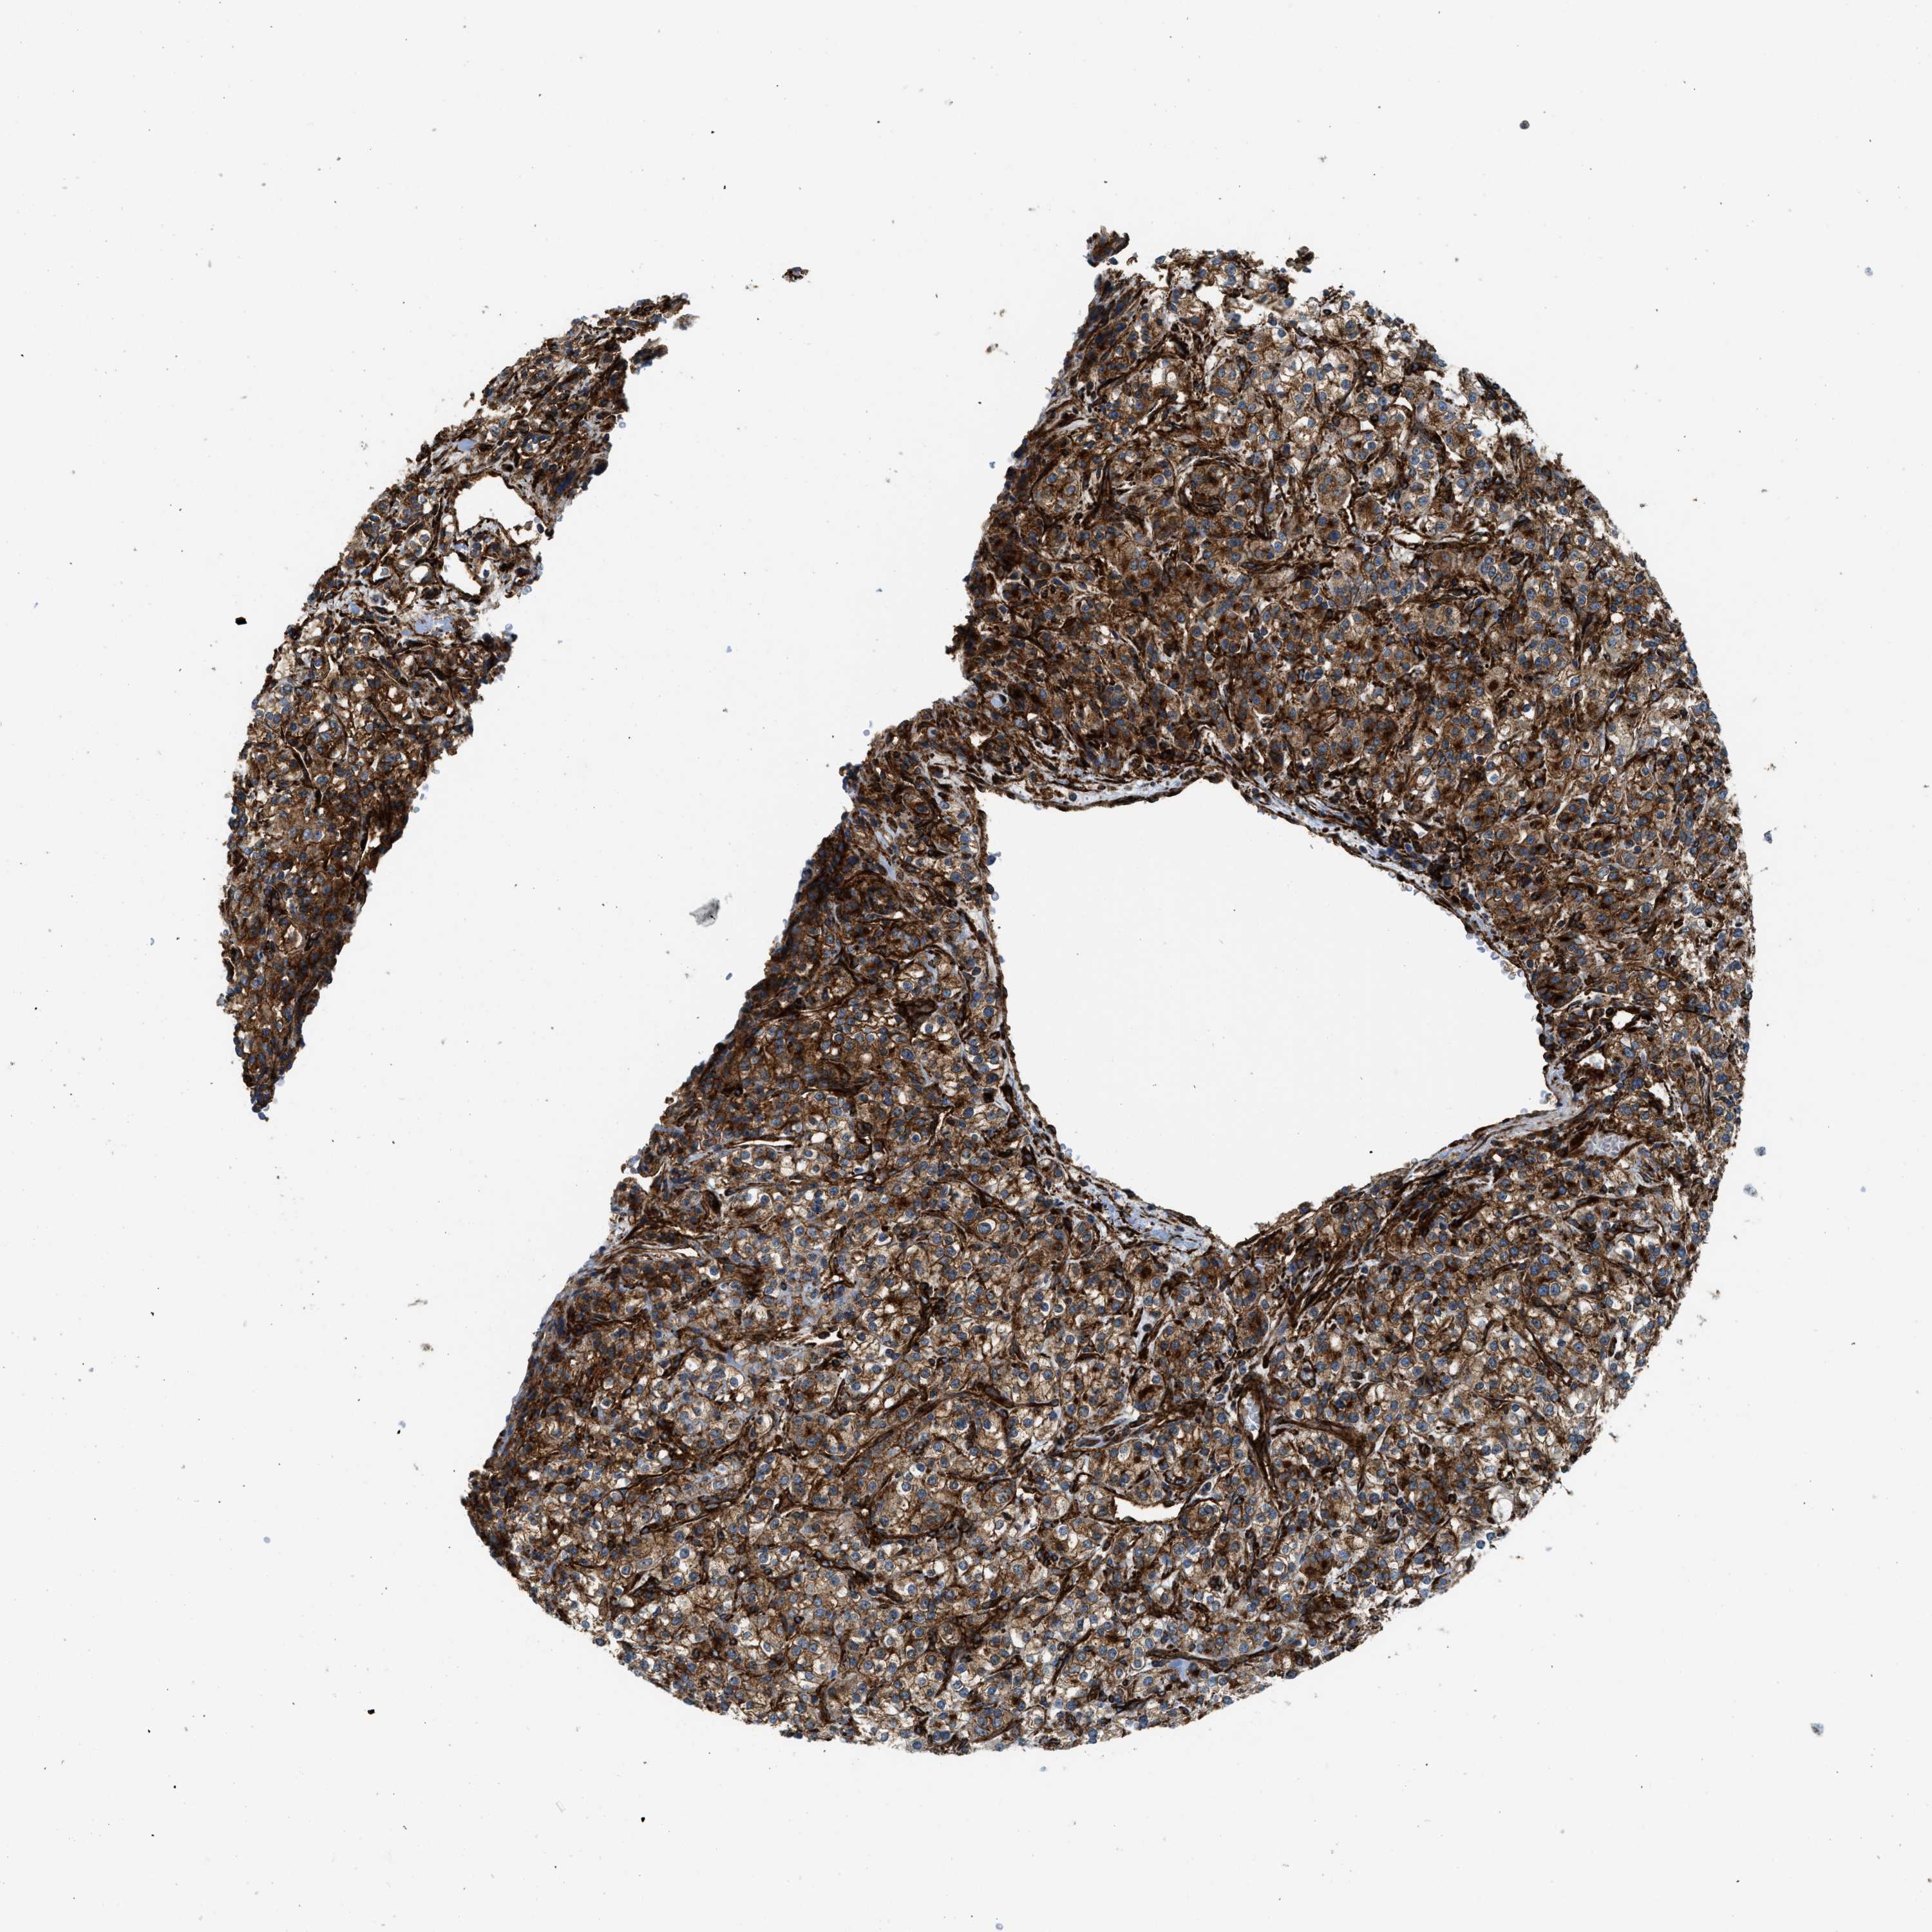

KIDNEY RENAL PAPILLARY CELL CARCINOMA (TCGA) - Interactive survival scatter ploti

The Survival Scatter plot shows the clinical status (i.e. dead or alive) for all individuals in the patient cohort, based on the same data that underlies the corresponding Kaplan-Meier plots. Patients that are alive at last time for follow-up are shown in blue and patients who have died during the study are shown in red.

The x-axis shows the expression levels (FPKM) of the investigated gene in the tumor tissue at the time of diagnosis. The y-axis shows the follow-up time after diagnosis (years). Both axes are complimented with kernel density curves demonstrating the data density over the axes. The top density plot shows the expression levels (FPKM) distribution among dead (red) and alive patients (blue). The right density plot shows the data density of the survived years of dead patients with high and low expression levels respectively, stratified using the cutoff indicated by the vertical dashed line through the Survival Scatter plot. This cutoff is automatically defined based on the FPKM cutoff that minimizes the p-score. The cutoff can be changed by dragging the vertical line or by entering a cutoff value in the square labeled "Current cut-off".

Under the Survival Scatter plot the p-score landscape (black curve; left axis) is shown together with dead median separation (red curve; right axis). Dead median separation is the difference in median mRNA expression between patients who have died with high and low expression, respectively. It is calculated as follows: median FPKM expression of dead patients with high expression - median FPKM expression of dead patients with low expression. This is intended to aid the user in visually exploring custom cutoffs and the associated p-scores and dead median separation.

Individual patient data is displayed and can be filtered by clicking on one or more of the category buttons on the top of the page. Categories describing expression level and patient information include: high, low, alive, dead, female, male and tumor stages. The scale of the x-axis can be toggled between linear and log-scale by clicking on the "x log" button. Mouse-over function shows TCGA ID, patient information and mRNA expression (FPKM) for each patient.

& Survival analysisi

Kaplan-Meier plots summarize results from analysis of correlation between mRNA expression level and patient survival. Patients were divided based on level of expression into one of the two groups "low" (under cut off) or "high" (over cut off). X-axis shows time for survival (years) and y-axis shows the probability of survival, where 1.0 corresponds to 100 percent.

HIP1 is not prognostic in Kidney Renal Papillary Cell Carcinoma (TCGA)

Best expression cut offi